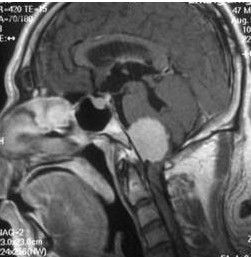

腦癌病變圖雖然沒有特定的臨床症狀可以直接判定惡性腦腫瘤的發生,但局部神經症狀例如顱內壓的產生和加重時則須相當注意,或是沒有癲癇病史的患者有突發性癲癇發作時有可能是由於腫瘤內的出血、腦水腫或腦脊液阻塞所引起,亦應提高警戒。

影像診斷在惡性腦腫瘤的判讀上是相當重要的。

影像檢查:除了臨床症狀的判斷,隨著科學的進步,影像檢查可快速並增加惡收腦瘤診斷的準確性,對於術後追蹤治療也相當有幫助。目前影像檢查包括有:

(1)電腦斷層掃瞄(ComputedTomography;CT);

(2)核磁共振攝影(MagneticResonanceImaging;MRI);

(3)腦波圖(Electroncephalography;EEG)以及腦血管攝影。

切片檢查:雖然影像檢查的進步,醫師常常可以藉由影像檢查來做腦病變的診斷,但有些情形更需要做切片檢查以確定病理診斷,尤其在腦瘤經評估是無法開刀切除時,切片手術有助於後續治療,目前切片檢查包括了立體定位切片檢查以及開顱切片檢查。